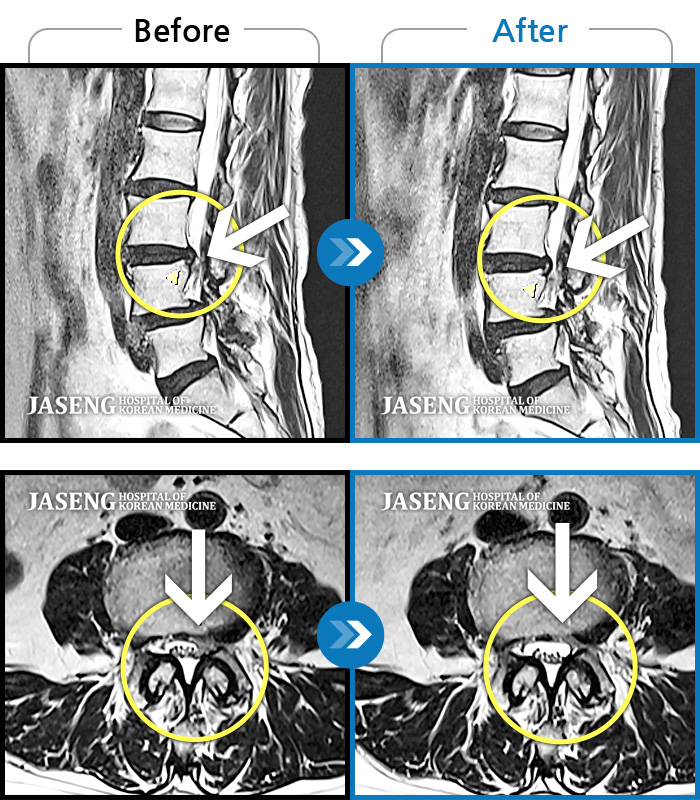

허리디스크

광주 · 김동은 원장

허리부터 골반 및 우측 허벅지에서 발가락까지 묵직한 통증과 저림 발생하여 내원하셨습니다.

촬영시기

2022.07.22 ~ 2025.08.18

2025.08.22

조회수 297